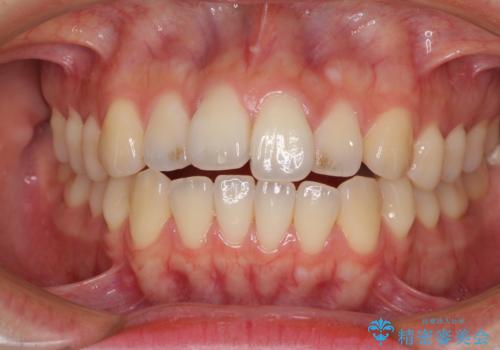

オープンバイトでかみにくい インビザラインによる矯正治療

- 前歯の上下スペースによる食べにくさを気にして来院された患者様です。

インビザラインにより上下の前歯の隙間を閉じていくこととしました。

上下の奥歯を圧下させるようにすることで、前歯を接触させるように計画しました。

上下の隙間に舌が入り込むことがオープンバイトの原因であったため、舌の筋肉のトレーニングも並行して行い、後戻りの抑制を図りました。